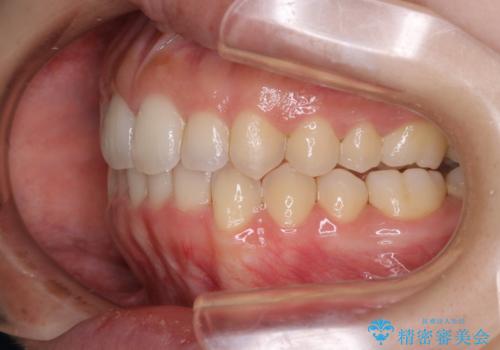

オープンバイト(開咬)を非抜歯インビザラインで治す

- 上下のがたつきを気にされてご相談にいらした患者さまです。

症状としてはオープンバイト(開咬)があり、舌癖も見られました。

オープンバイトの方への治療は、通常抜歯を行いワイヤーによる矯正治療を行うことが多いですが、今回はインビザラインの特性を生かし、非抜歯にて綺麗な歯並びを作ることが出来ました。